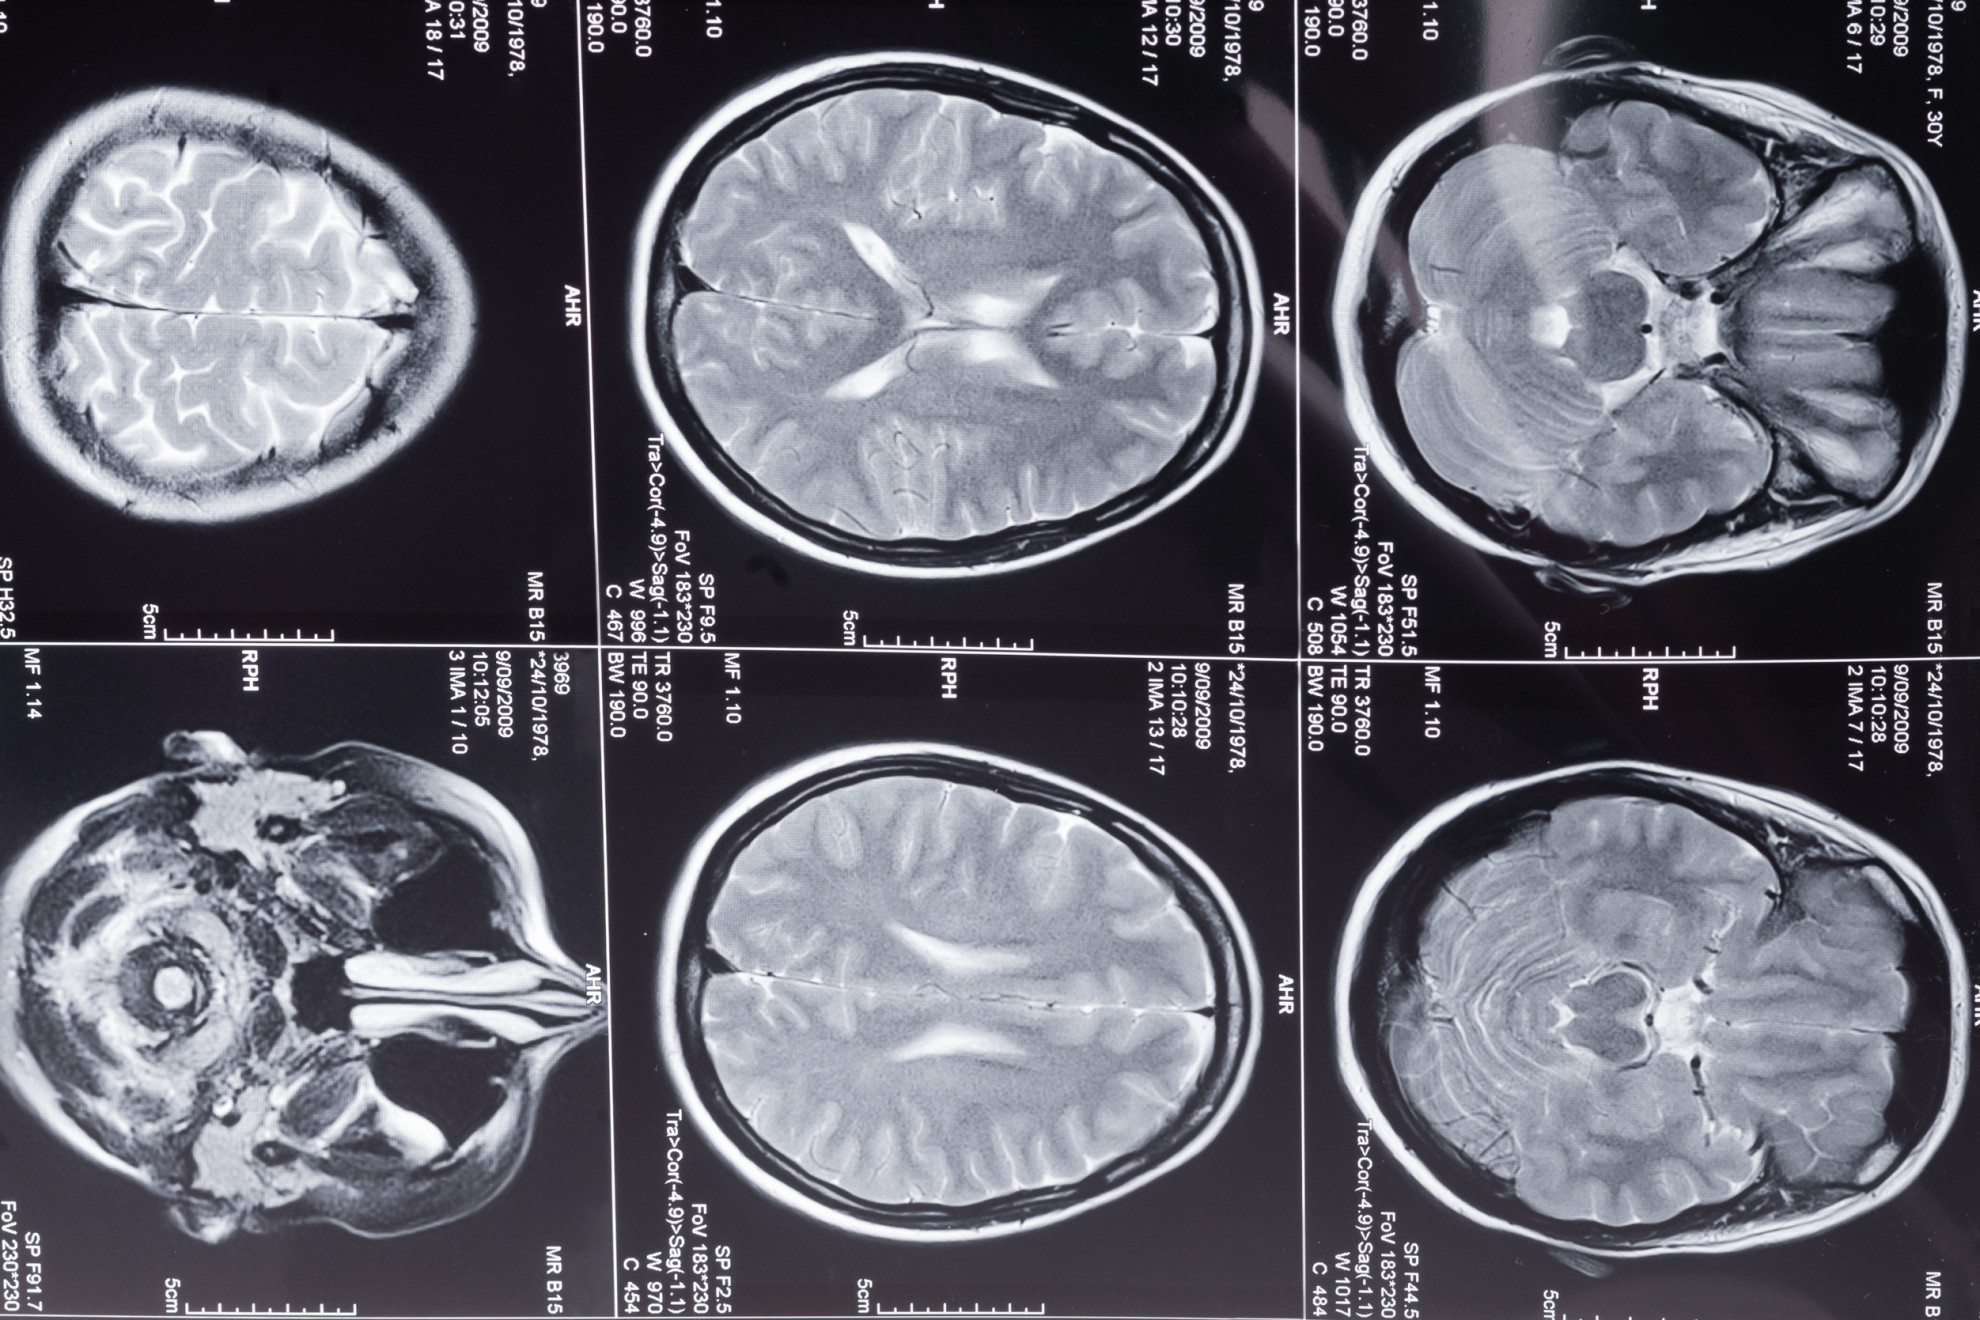

Анализ показал, что у женщин, применявших депо-медроксипрогестерона ацетат, риск развития менингиомы оказался в 2,43 раза выше, чем у не использовавших гормональную контрацепцию. При пероральном приеме медроксипрогестерона ацетата риск был повышен в 1,18 раза.

Риск развития менингиомы увеличивался только у женщин, принимавших препарат больше четырех лет или начавших его использование после 31 года. В то же время комбинированные пероральные контрацептивы и внутриматочные спирали были связаны со снижением риска развития опухоли.

Авторы заключили, что длительное применение депо-медроксипрогестерона ацетата связано с повышенным риском развития менингиомы, в то время как другие методы контрацепции такого эффекта не продемонстрировали. Полученные результаты могут помочь врачам при обсуждении баланса пользы и риска с пациентками, особенно имеющими дополнительные предрасполагающие факторы.